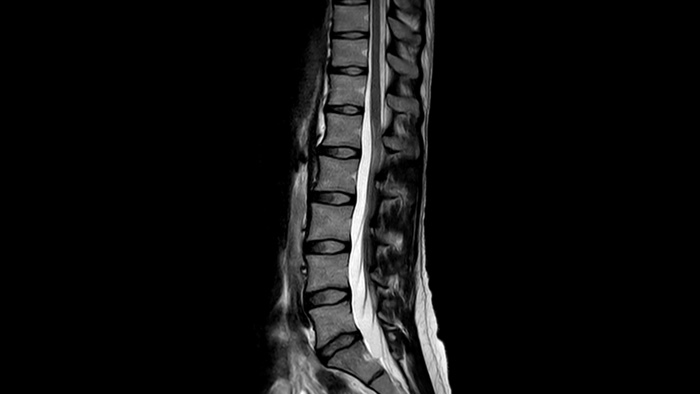

SmartSpeed SmartSpeed AI enables to decrease the scan time up to 65% with equal or better image quality

Diagnostic confidence Expand your imaging capabilities in all clinical areas. See how your peers are benefiting.

Speed & Comfort Provide up to 40% reduction in breath holds, with virtually equal image quality4.